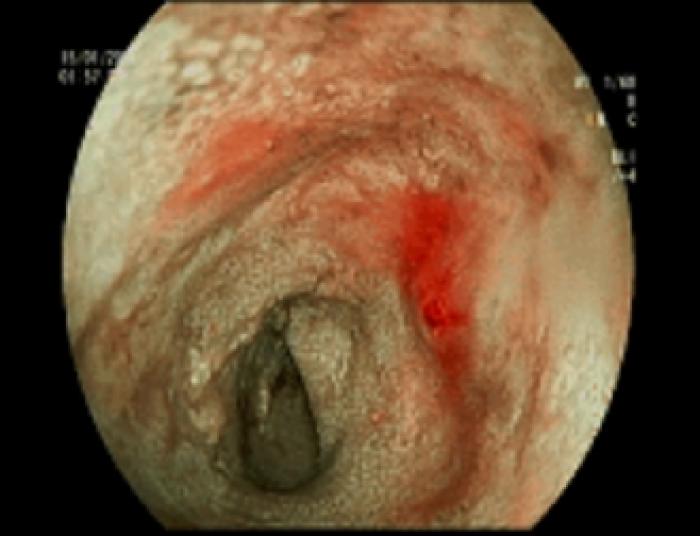

- Colitis e ileítis congestiva ligera (Figura 5)

- Duodenitis congestiva y erosiva moderada (Figura 13)